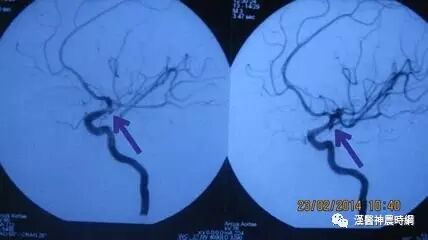

4.烟雾病 年龄多在10岁以下及20~40岁,儿童常表现为脑缺血性症状伴进行性智能低下,成人多为脑出血性症状,但意识障碍相对较轻,脑血管造影可见颅底特征性的异常血管网,以资鉴别。

未破裂动脉瘤有局部症状或颅内压增高表现者,以及破裂出血引起蛛网膜下腔出血者尚需要与颅内肿瘤,脑血管畸形,高血压性脑出血,烟雾病,颅脑损伤,血液病,脊髓血管畸形等疾病相鉴别。